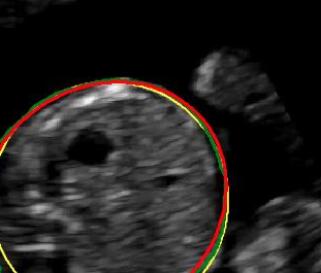

Sound-opaque occluders, including bones and calcified tissues, block the propagation of sound waves by strongly absorbing or reflecting sound waves during scanning. The regions behind these sound-opaque occluders return little to no reflections to the US transducer. Thus these areas have low intensity but very high acoustic impedance gradients at their boundaries (e.g. Fig. 1(a) left column). Reducing acoustic shadows and correct interpretation of images containing shadows rely heavily on sonographer experience. Experienced sonographers avoid shadows by moving the probe to a more preferable viewing direction during scanning or, if no shadow-free viewing direction can be found, a mental map is compounded with iterative acquisitions from different orientations.

We propose a novel method based on convolutional neural networks (CNNs) to automatically estimate pixel-wise confidence maps of acoustic shadows in 2D US images. Our method learns an initial latent space of shadow regions from images consisting of multiple anatomies and with global image-level labels (“has shadow” and “shadow-free”), e.g. Fig. 1(a). The basic latent space is then estimated by learning from fewer images of a single anatomy (fetal brain) with coarse pixel-wise shadow annotations (approximately of the images with global image-level labels), e.g. Fig. 1(b). The resulting latent space is then refined by learning shadow intensity distributions using fetal brain images so that the latent space is suitable for confidence estimation of shadow regions. By using shadow intensity information, our method can detect more shadow regions than the coarse manual segmentation, especially relatively weak shadow regions.